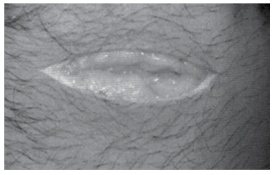

A figura, embora sem sinais vitais, refere-se a ferimento causado por navalha. O agente e a lesão recebem, respectivamente, o nome de agente